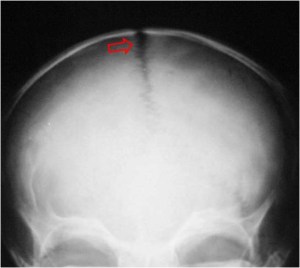

SIGNO DEL ALGODÓN

El signo del algodón hace referencia al aspecto que tiene el hueso en la radiografía de cráneo en pacientes con enfermedad de Paget. Se observa un engrosamiento de la calota en la que existen focos de esclerosis parcheados y de aspecto borroso que resaltan sobre un hueso de menor densidad.

En la literatura angloamericana también se ha descrito el Signo de Tam O´shanter para describir la afectación por enfermedad de Paget de la calota. El Tam O´shanter es la boina escocesa, que recibe el nombre del personaje de un poema narrativo de Robert Burns publicado en 1791. Con este nombre se describe el aspecto del cráneo en la proyección lateral, como envuelto por una boina o gorro.